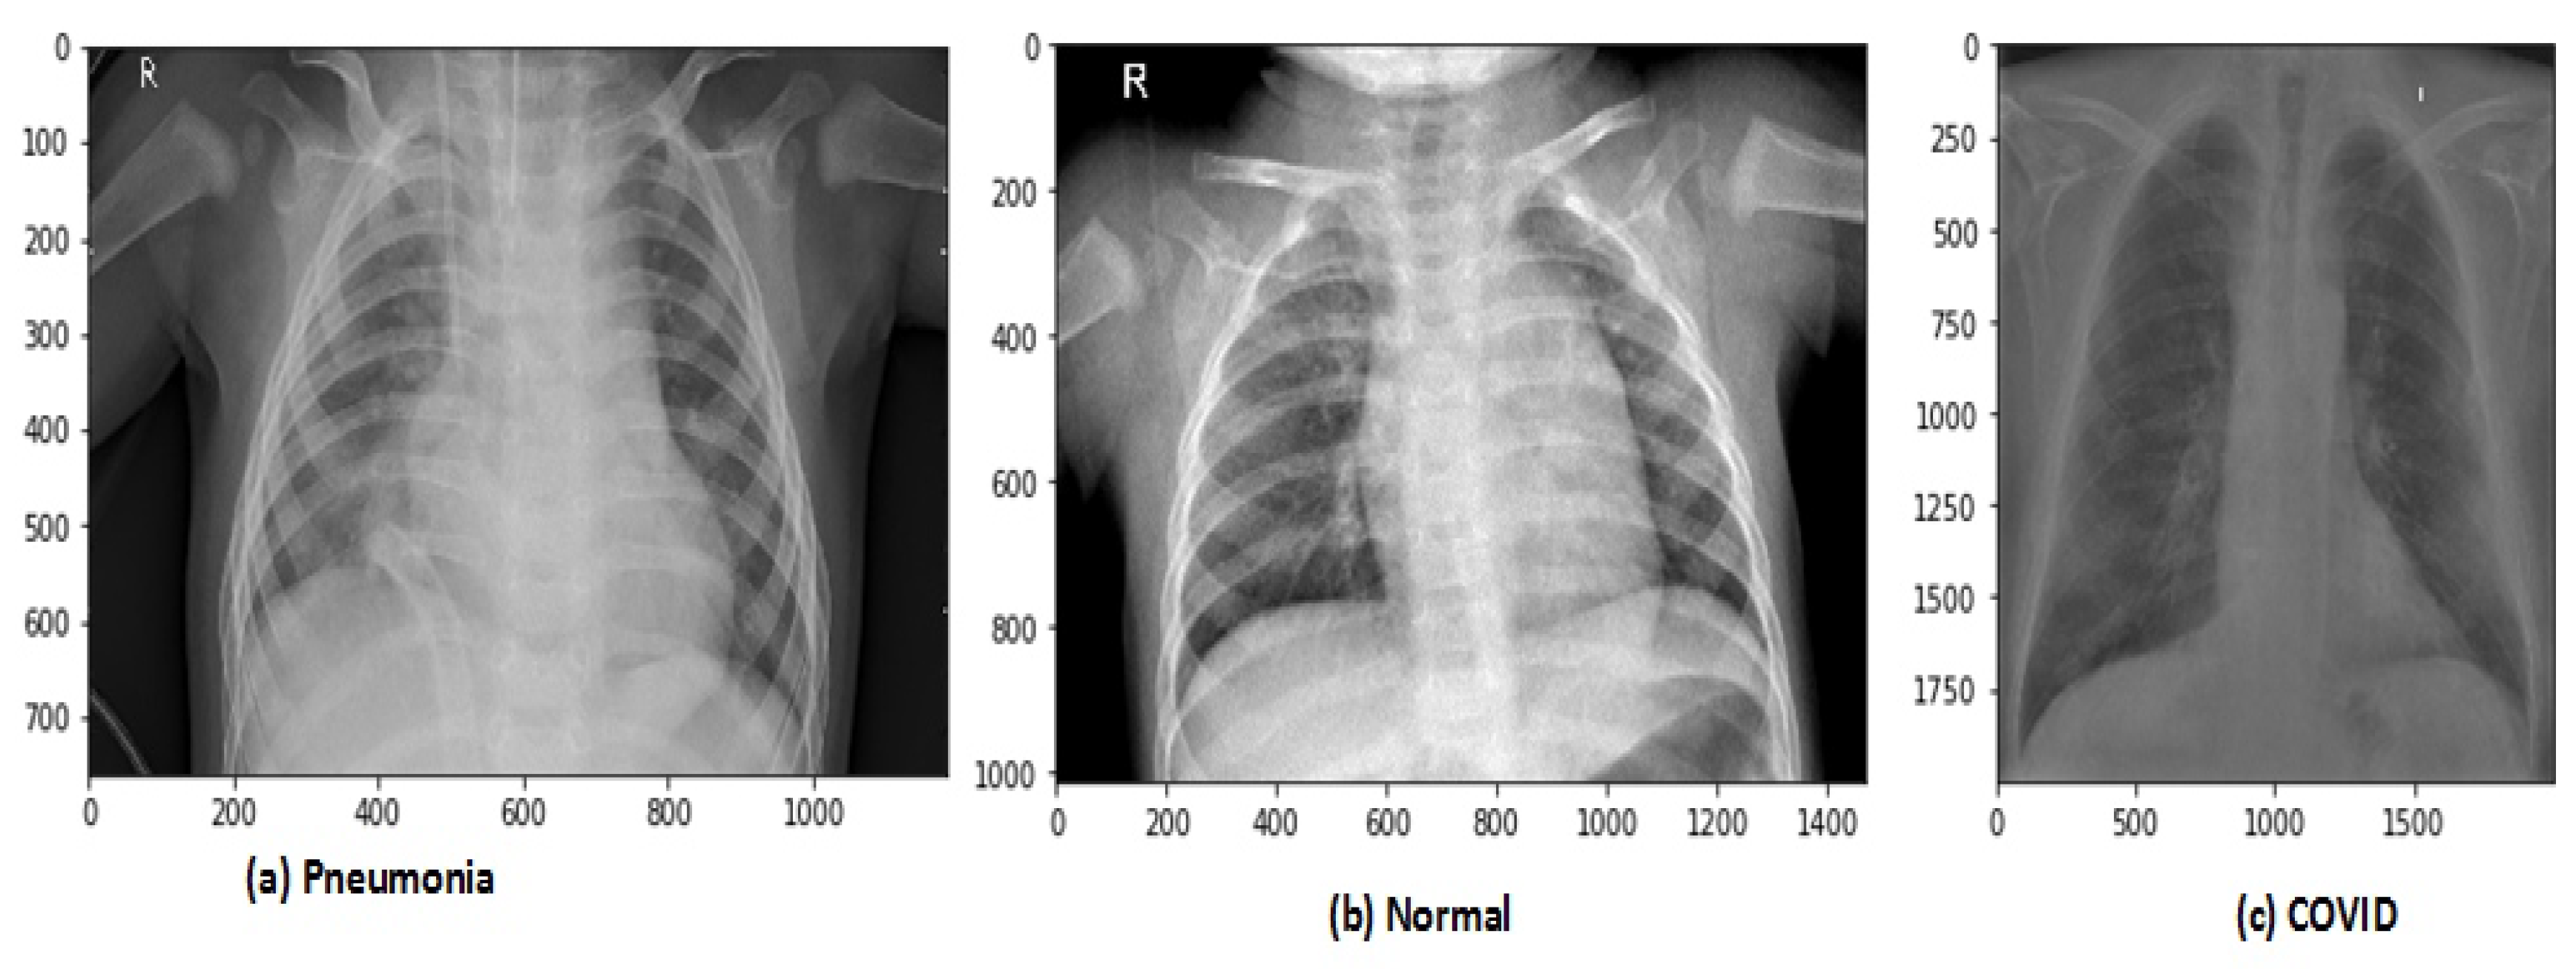

After data augmentation, the images in the new dataset are 12,864. The proposed model has trained on original and augmented data sets, respectively, for all experiments. The holdout cross-validation method has used for the training and validation process in the proposed model because the data sets are now large enough so it will not make computational complexity problems and model will fit exactly and will generate high performance. The images of CRD and CXI datasets are shown in Figure 3 and Figure 4.

Figure 4.

Types of chest X-ray images in CXI data set.

To increase the data set size for effective training of the 2DCNN model we have used the data augmentation technique to augment the original dataset by using random transformation (rotation). All the images have been rotated with an angle of 45 degrees along the X-axis and added these augmented images to the original data set. Thus, the total images in new data are 42,330. The data augmentation technique has also used on the second chest X-ray (Covid-19 and Pneumonia) (CXI) data set. This data set has chest X-ray 6432 images, which belong to three classes (COVID19, Normal, PNEUMONIA). The data set contain 576 COVID19, 1583 Normal, and 4273 PNEUMONIA images, respectively.